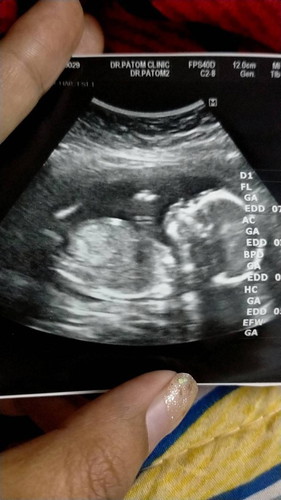

เด็กอ้วนเริ่มโตแล้วค่ะ ทราบเพศน้องแล้วค่ะ baby boy ค่ะ

แม่ๆบ้านอื่นน ทีมไหนกันบ้างคะ เด็กน้อย 17 วีคเด็กอ้วนน #ขอบคุณล่วงหน้านะคะ #ท้องแรกคะ #ขอบคุณสำหรับคำตอบค่ะ

17w5d วันนี้หมอนัด อยากรู้เพศแล้วค่ะตื่นเต้น 😂 คุณพ่อเขาอยากได้ลูกชายมากๆ แต่อิแม่แอบอยากได้ลูกสาว 😅

น้องหนักกี่กรัมค่ะเเม่ บ้านนี้ท้องเเรกเหมือนกัน 17w6วัน น้องหนัก217กรัม

17W เท่ากันเลยค่ะแม่ บ้านนี้ลูกสาว ทีมสิงหาคม66 ค่ะ🥰

บ้านนี้21Wเด็กอ้วนน้ำหนัก470แร้วคะ ดช ทีมกรกรฎาคมคะ